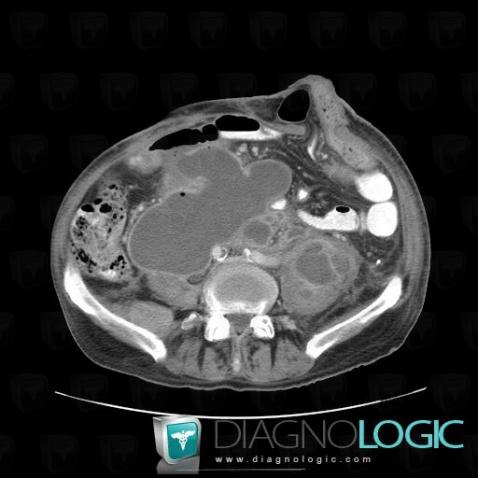

Abscess, Retroperitoneum, CT

Here is the specific information in the key image above:

- Diagnosis Abscess, Location(s) Retroperitoneum, with gamuts Lesion in the psoas space